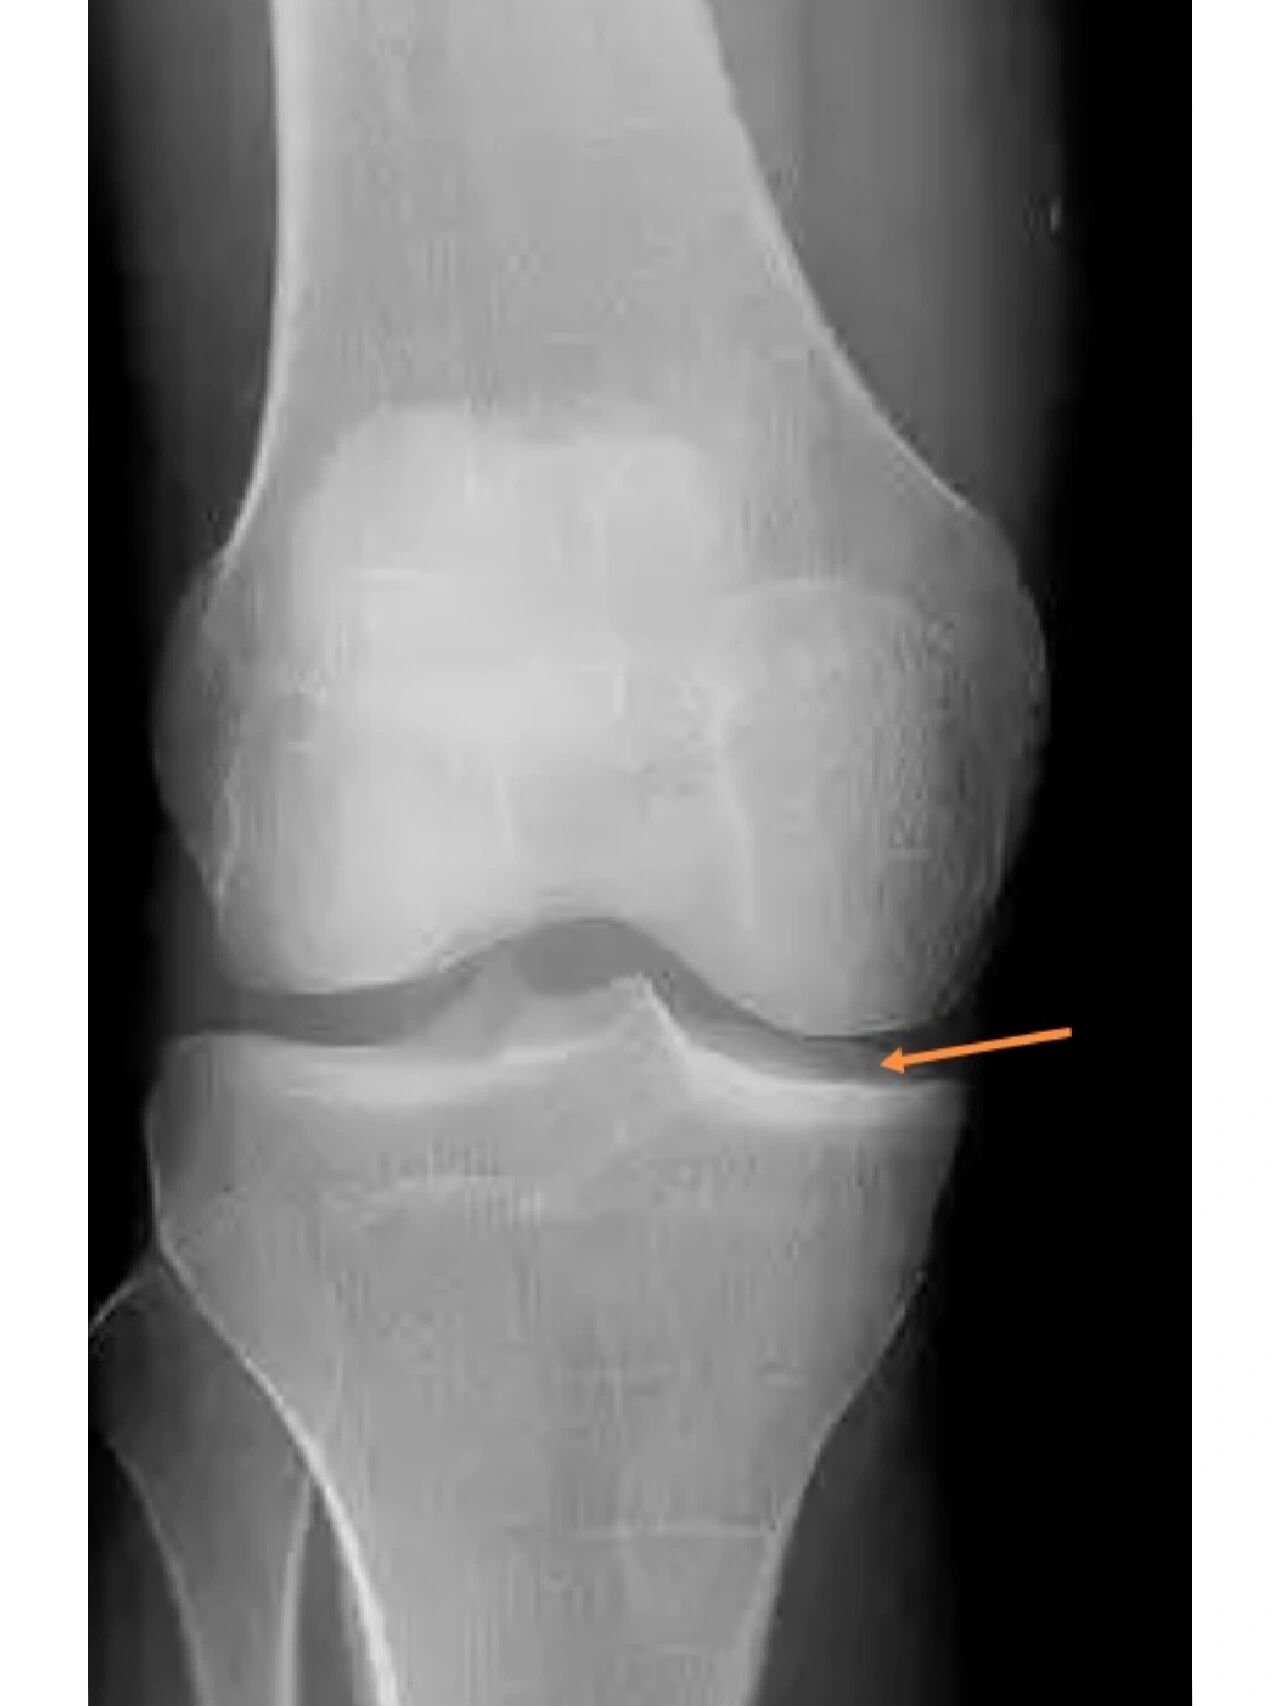

怎么拍出标准的膝关节正侧位片? 我们先来看看一张标准的膝关节正位.

2401骨肌影像病例一张膝关节正侧位片你能精准诊断吗有结果